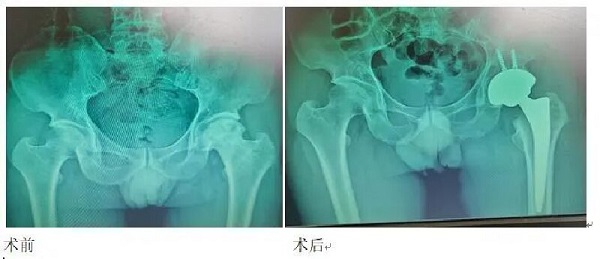

近日我院骨一科独立完成一例微创直接前方入路人工全髋关节置换手术(DAA-THA),标志着我院关节外科水平再上新台阶。患者术后恢复良好,行动自如,疼痛明显减轻。术后获得了早期的快速康复,行走更加自然。

髋关节置换被誉为现代关节外科最为成功的手术之一,其手术入路也呈现多样化,目前国内最为广泛应用的手术入路是从后方和外侧进入髋关节做手术。使用这些入路开展手术,需要切开一些肌肉以后才能显露髋关节,损伤也较大,而且都有一定的脱位率,患者手术后需要避免下蹲、盘腿、低坐等各种束缚来防止关节脱位。

1.因为DAA入路是在肌肉的间隙直接进入关节,并不会破坏髋关节周围重要的软组织,手术后的疼痛感会非常轻微,手术体验感非常好,患者术后步态更加自然。

2.手术以后不需要过多的活动限制,只要身体状况许可,麻醉清醒后患者就可以做任何活动,行走、上厕所、下床、下蹲、跷二郎腿、穿袜都不用有任何顾虑。

微创和快速康复是医患共同追求的目标。DAA入路髋关节置换损伤小,可以满足快速康复的需求,真正让患者受益,让髋关节患者尽早出院,尽早恢复关节功能。